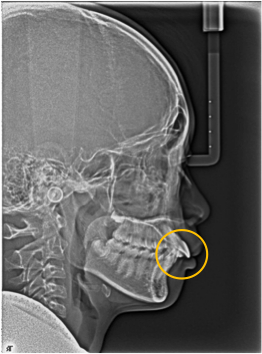

図の2〜5は同じ人のレントゲン写真ですが、前歯と6歳臼歯の間の乳歯が抜けて、永久歯に生え変わった後に6歳臼歯の後ろから第二大臼歯が生えてきています。

図4 13歳時 乳歯は全て永久歯に生えかわり第二大臼歯の萌出前

図5 15歳時 第二大臼歯の萌出中